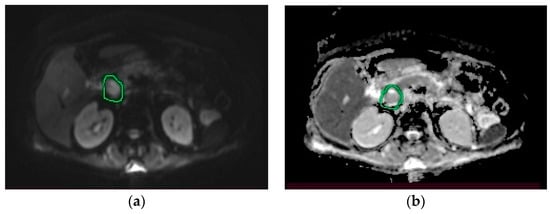

2. Case Presentation